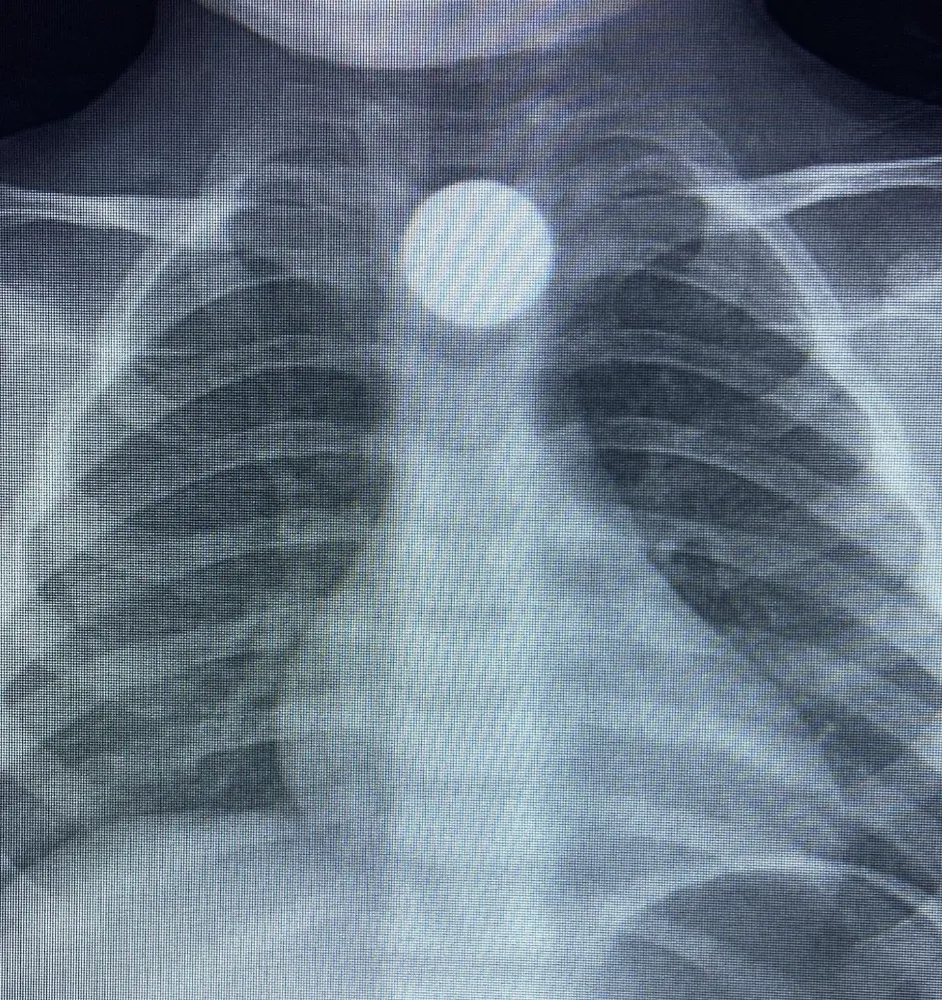

Yapılan kontrollerde, 50 kuruşun yemek borusunda takılı kaldığı belirlendi. Minik Bilal’in tedavisi sürerken, olayla ilgili soruşturma başlatıldı. Yetkililer, özellikle küçük çocukların evde bulduğu madeni para ve küçük eşyalar konusunda ailelerin dikkatli olması gerektiğini vurguladı.